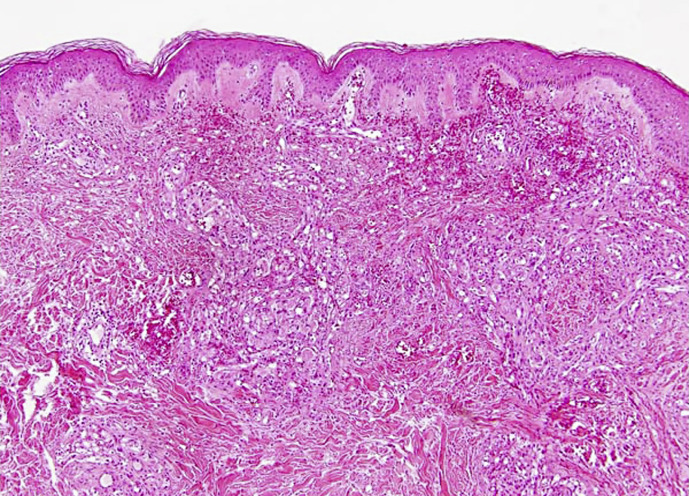

Introduction: Reactive angioendotheliomatosis (RAE) is a rare, benign, angioproliferative disorder with poorly understood aetiopathogenesis. It is characterised by vascular occlusion that occurs in patients with coexistent systemic or autoimmune disease.

Case presentation: A 60-year-old female presented with an 8-week history of a painful, non-healing, and non-traumatic ulcer on the left thigh. Her past medical history included smoking, peripheral vascular disease (PVD) and previously treated rectal squamous cell carcinoma. The diagnosis of pyoderma gangrenosum with superimposed cellulitis was considered and treatment with oral antibiotics was initiated. Following failure to improve, a biopsy was undertaken leading to the diagnosis of RAE. The patient was referred for urgent consideration of surgical correction of PVD, but was deemed unsuitable for surgical treatment due to a poor performance status. The patient was treated with conservative measures, but her condition rapidly deteriorated and she passed away a few weeks later.

Conclusion: RAE is notorious for mimicking a wide spectrum of diseases. It is an important differential diagnosis to consider in patients with non-healing ulceration and underlying systemic or autoimmune disorders. Our case raises awareness of this rare condition and the mortality that it carries if left untreated. In an attempt to reverse disease progression and mortality, we urge clinicians to attempt surgical correction of PVD even when faced with multiple comorbidities and poor performance status.